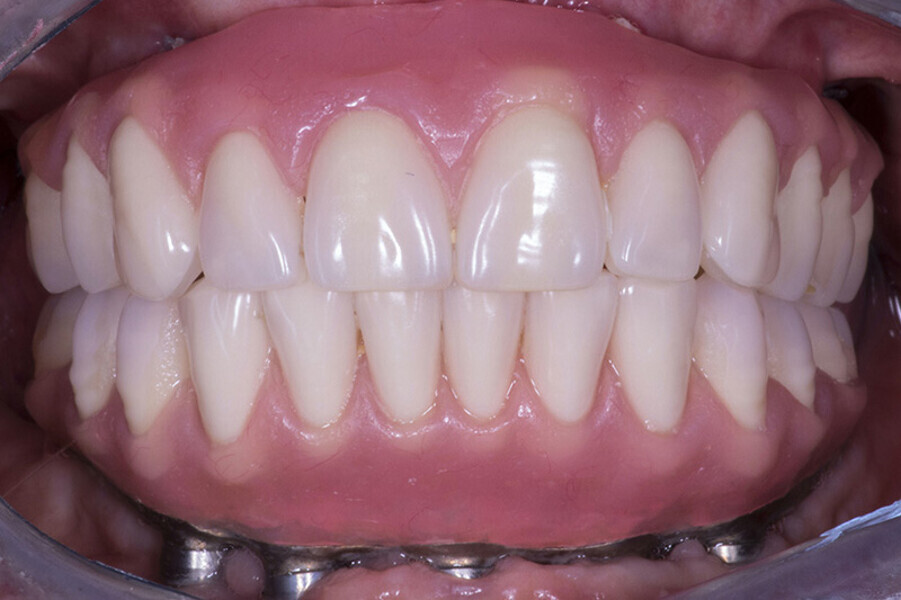

Fig. 4 Prótesis Híbrida inmediata y radiografía control con 6 años post-operatorio

Fig. 5. Prótesis Híbrida inmediata y radiografía control con 6 años post-operatorio

Fig. 6. Prótesis Híbrida inmediata y radiografía control con 6 años post-operatorio